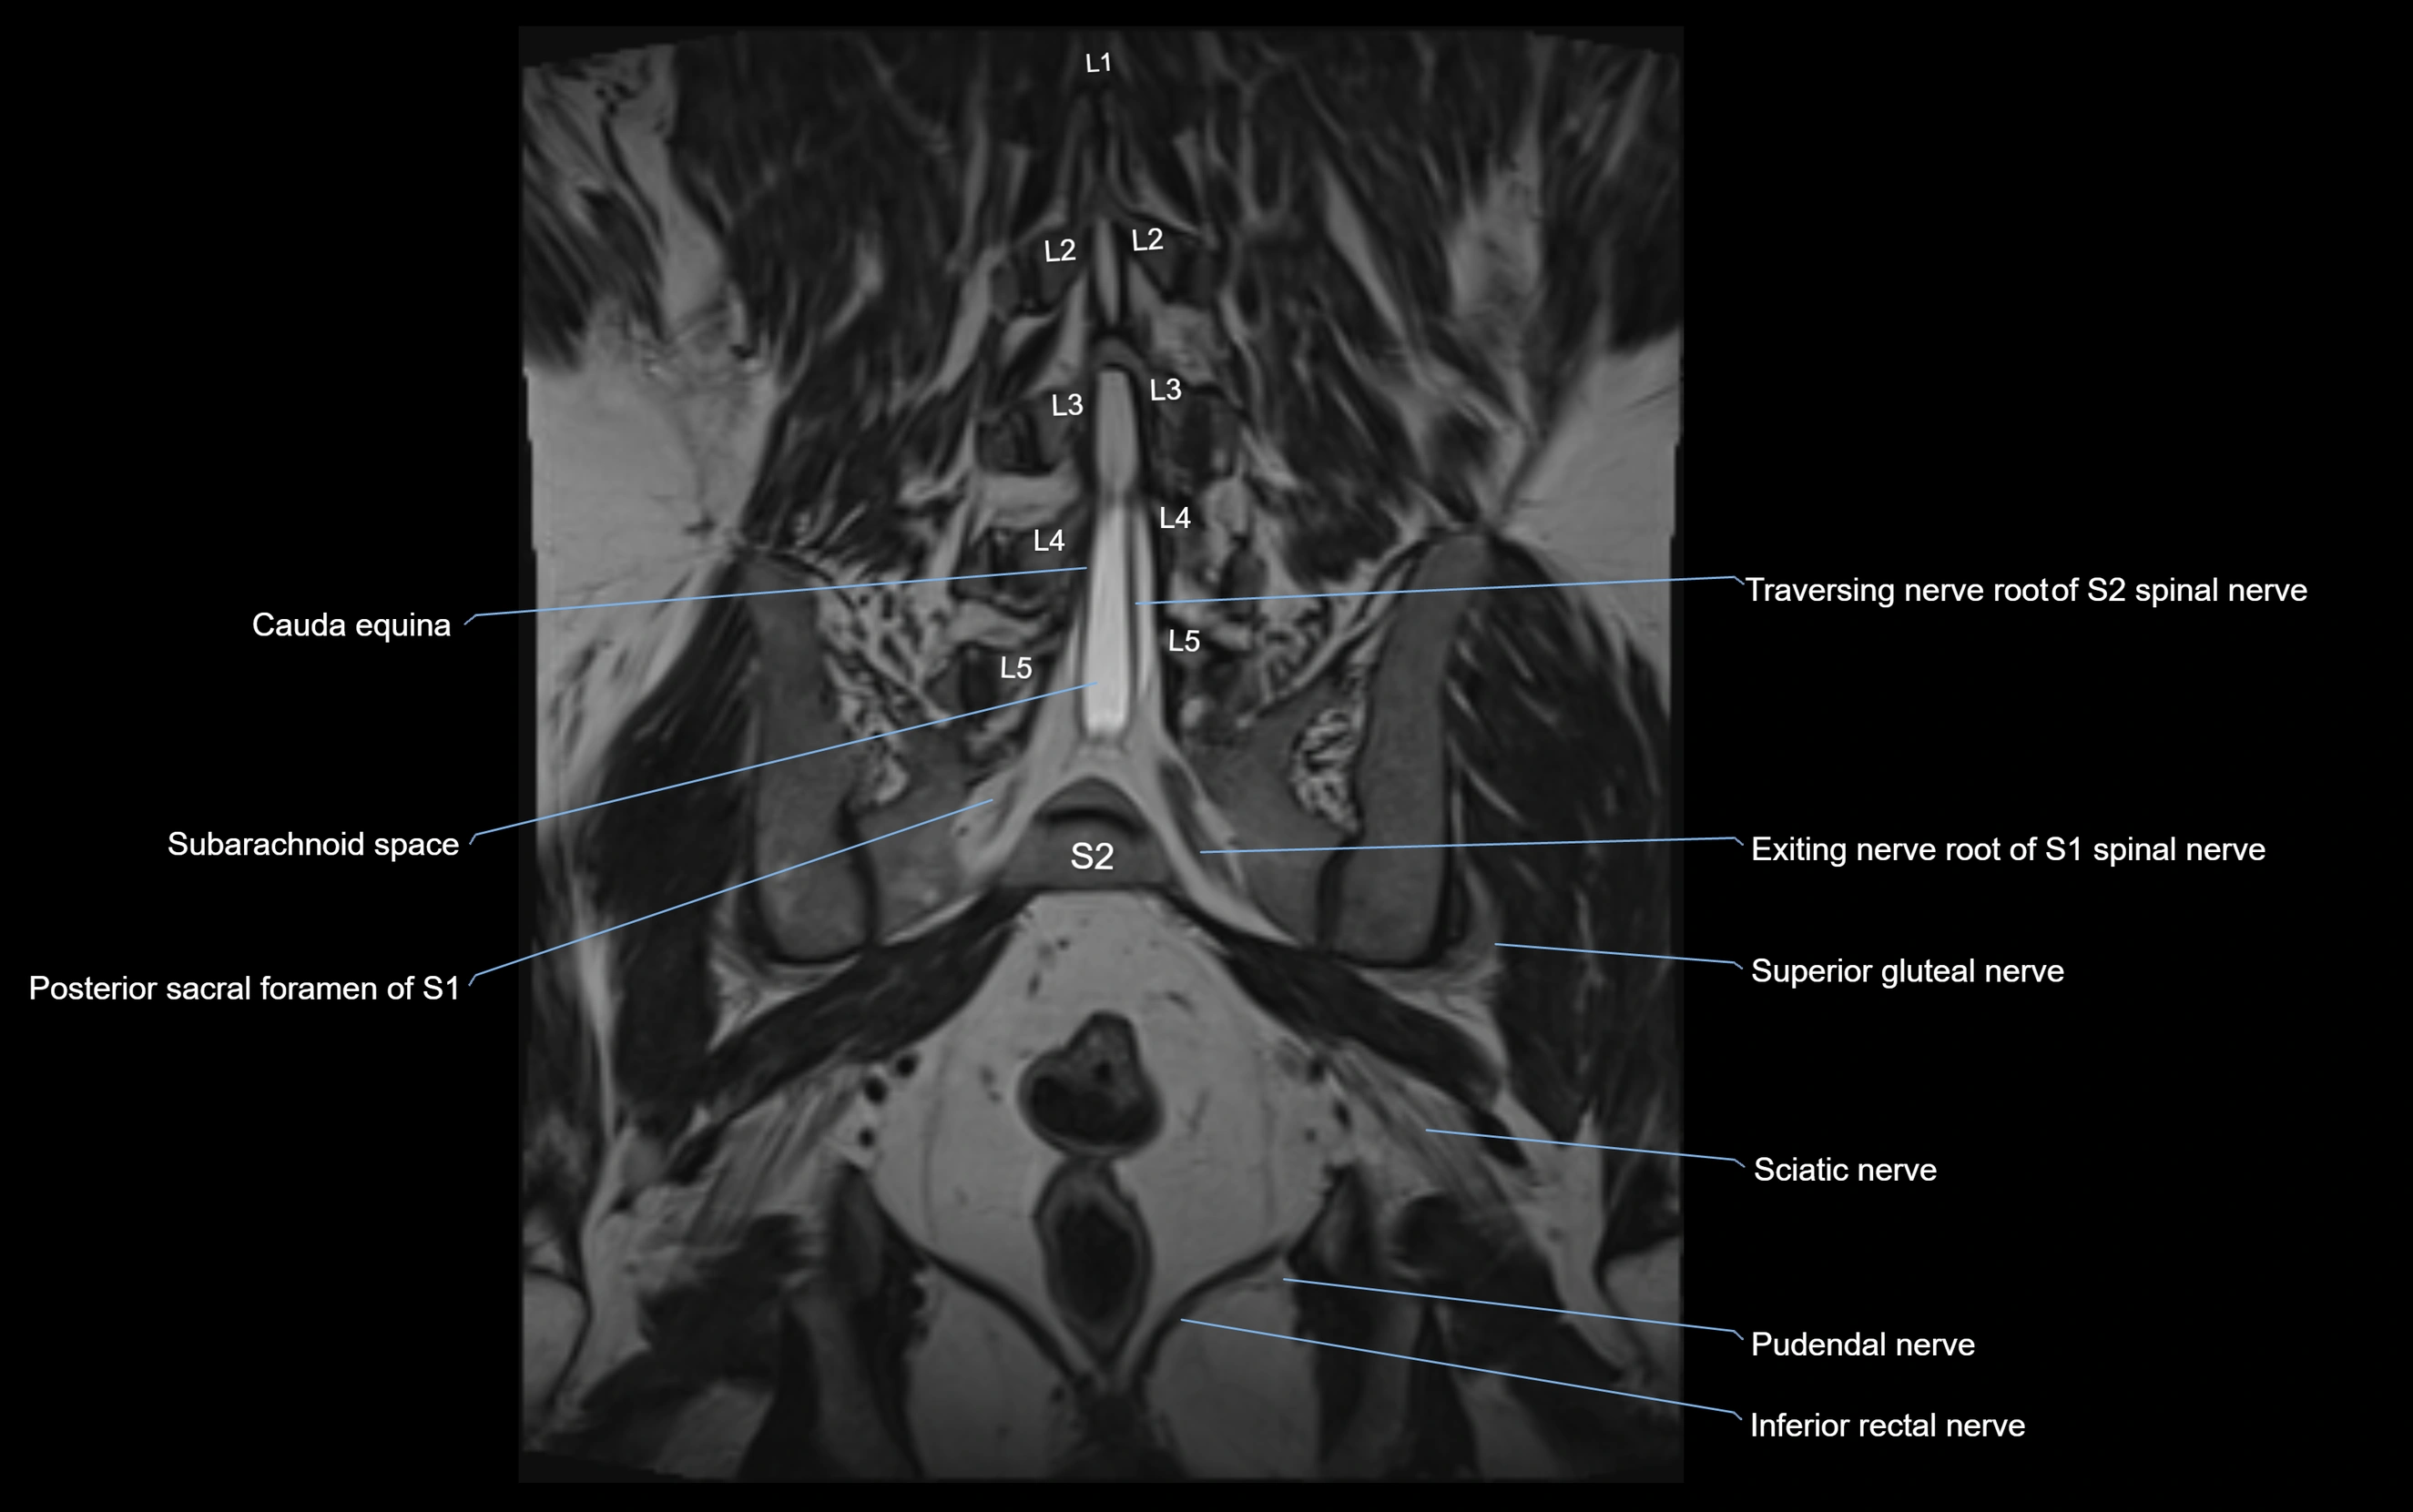

MRI image

image